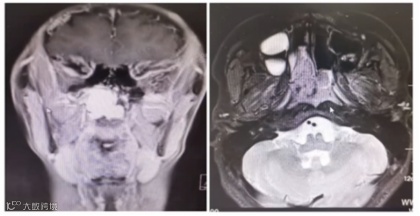

MRI检查:右侧鼻腔中后部见不规则团块影,病灶信号混杂,以稍长T1、T2信号为主,局部见长T1、T2信号影。左右径3.1cm,前后径3.7cm、上下径3.9cm。病灶边界欠清,向后突入鼻咽腔及右侧蝶窦,向上达鼻咽顶壁,下达软腭平面。增强扫描后病灶早期强化明显,延迟期病灶持续强化。(见下图)